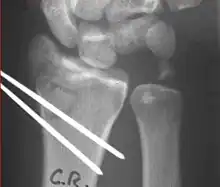

Surgery is generally indicated for displaced or unstable fractures.[18] The techniques of surgical management include open reduction internal fixation (ORIF), external fixation, percutaneous pinning, or some combination of the above. The choice of operative treatment is often determined by the type of fracture, which can be categorized broadly into three groups: partial articular fractures, displaced articular fractures, and metaphyseal unstable extra- or minimal articular fractures.[5]

Surgical options have been shown to be successful in patients with unstable extra-articular or minimal articular distal radius fractures. These options include percutaneous pinning, external fixation, and ORIF using plating. Patients with low functional demand of their wrists can be treated successfully with nonsurgical management; however, in more active and fit patients with fractures that are reducible by closed means, nonbridging external fixation is preferred, as it has less serious complications when compared to other surgical options.[5] The most common complication associated with nonbridging external fixation is pin tract infection, which can be managed with antibiotics and frequent dressing changes, and rarely results in reoperation.[5] The external fixator is placed for 5 to 6 weeks and can be removed in an outpatient setting.[5]

Displaced intra-articular fractures

These fractures, although less common, often require surgery in active, healthy patients to address displacement of both the joint and the metaphysis. The two mainstays of treatment are bridging external fixation or ORIF. If reduction can be achieved by closed/percutaneous reduction, then open reduction can generally be avoided. Percutaneous pinning is preferred to plating due to similar clinical and radiological outcomes, as well as lower costs, when compared to plating, despite increased risk of superficial infections.[24] Level of joint restoration, as opposed to surgical technique, has been found to be a better indicator of functional outcomes.[5]